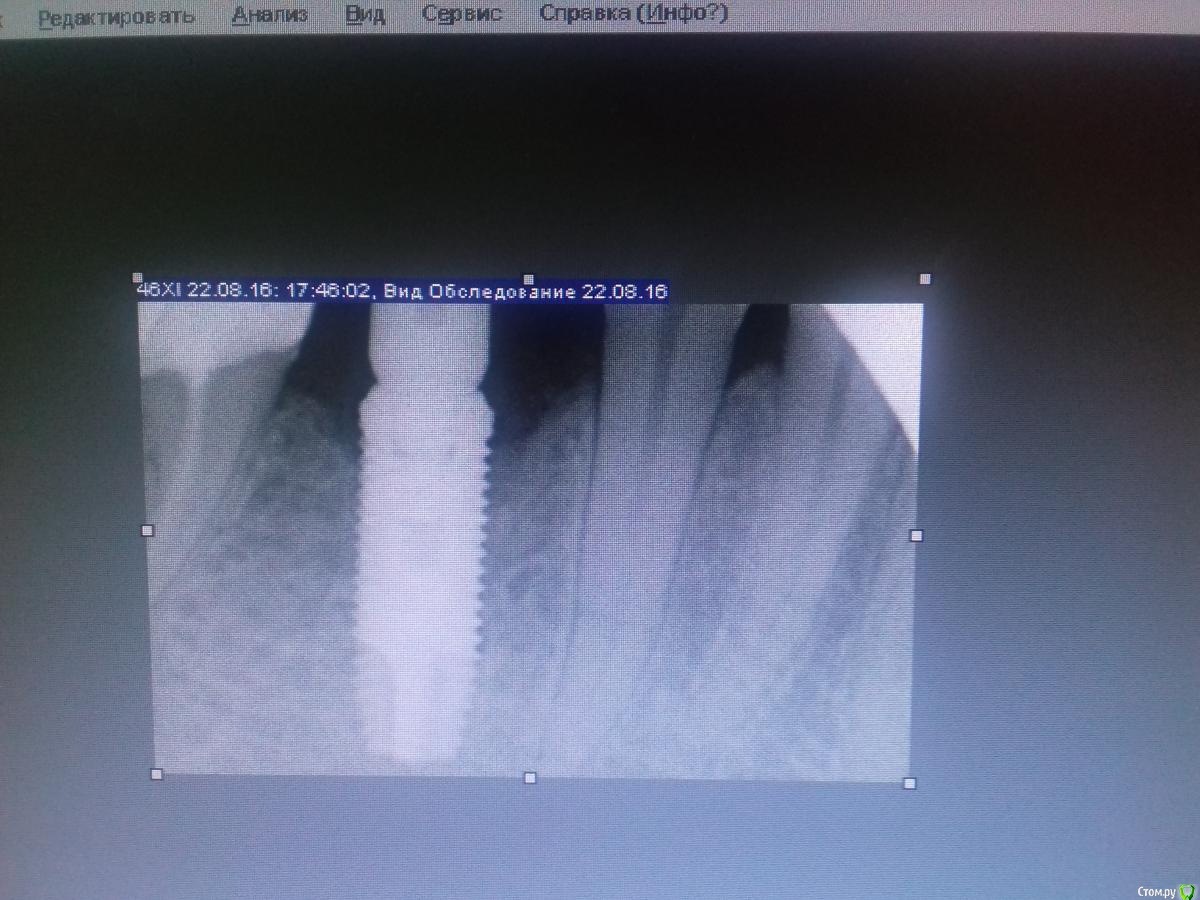

Jurai Опубликовано 25 декабря, 2016 Поделиться Опубликовано 25 декабря, 2016 *Предупреждение: фото на "мыльницу", не все этапы удались, но я работаю над этим) Вот пациент. Приятнейший, во всех отношениях, с негативным отношениям к мостовидным конструкциям. Полтора года лечил 41з по поводу периодонтита: толку не вышло. Удалил у широко известного многим стоматологам, особенно выпускам последних годов, доктора с ученой степенью. После удаления 4 месяца, по КТ область вполне достойно выглядит. Вот с чем пришел, обычное дело, все прилично: Раскрываю, а там между тонкими кортикалками мягко и упруго - резидуальная, фото нет. Открываю сильнее чем обычно, с расстройства не особо удачно. Кюретаж : Вид после, ушла вестибулярная кортикальная вместе с кистой: Сверлим 2,0, позиционердля рентген-контроля Имплантат ADIN UNP2,75Х11,5мм Ауто, джейсон коллагенфлис (что было под рукой) Швы. Контроль, перещелкивать не стали. В общем, понравился имплантат, для себя пометку кюретажить тщательнее, не надеяться, что организм все переварит. 1 9 Ссылка на комментарий